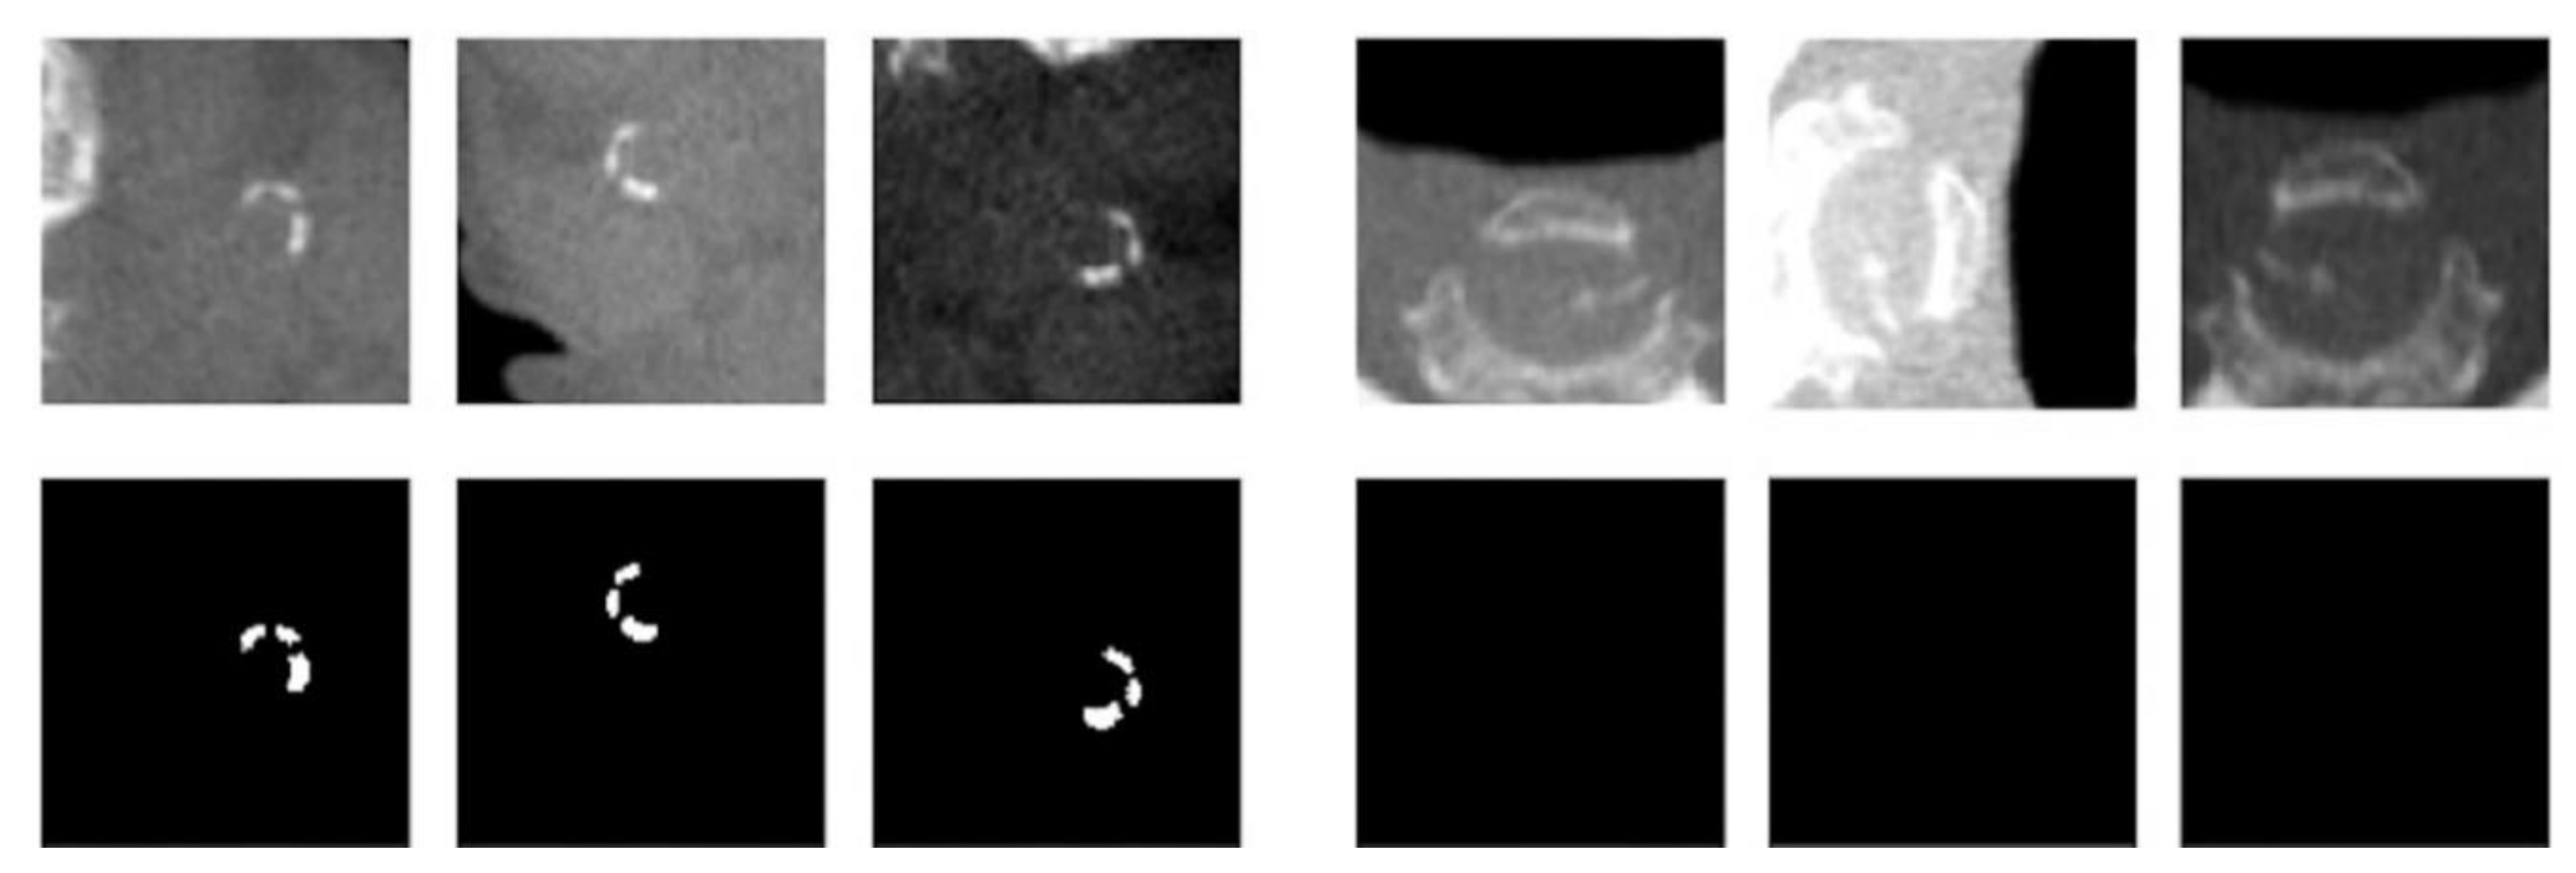

1. Introduction

2.2. Step 2: Detection and Localization of Calcifications

2.2.1. Method A

2.2.2. Method B